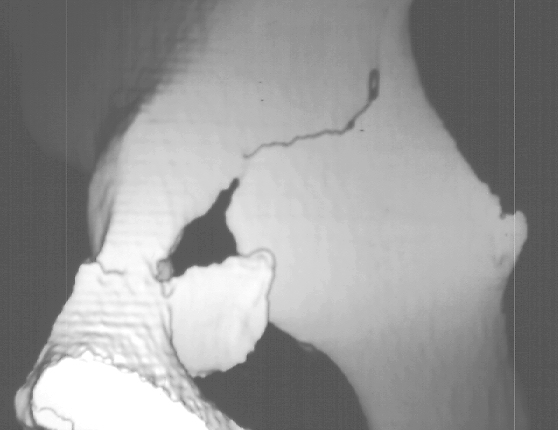

A 16 year old female was previously in good health when she was involved in a roll-over motor vehicle accident as an unrestrained passenger, and ejected from the vehicle. She landed in a field. She was taken by ambulance to a nearby hospital complaining of pain in the pelvis. An x-ray of her pelvis was obtained (image 1), Obturator and iliac oblique(image 2), A CT scan of the fracture was obtained (images 3, 4 & 5).

An absolute indication for open reduction in this case would be if the hip joint is not completely reduced.

If an open reduction is planned the best approach would be the ilioinguinal approach.